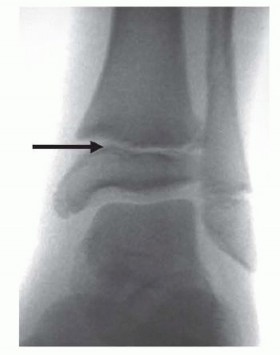

Chapter 35 Pediatric Ankle Fractures Scott J. Mubarak Andrew T. Pennock DEFINITION Ankle fractures account fo…